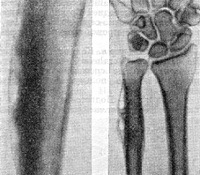

Сопровождается резкими болями, значительным отеком мягких тканей, повышением температуры тела и симптомами общей интоксикации. В области поражения прощупывается широкая бугристость, резко болезненная при пальпации. При проведении рентгенографии на начальных стадиях изменения отсутствуют. В последующем определяется утолщение надкостницы, при переходе воспаления на кость выявляются признаки остеомиелита. Лечение - вскрытие параоссальных флегмон или поднадкостничных абсцессов на фоне антибиотикотерапии и общеукрепляющих мероприятий.